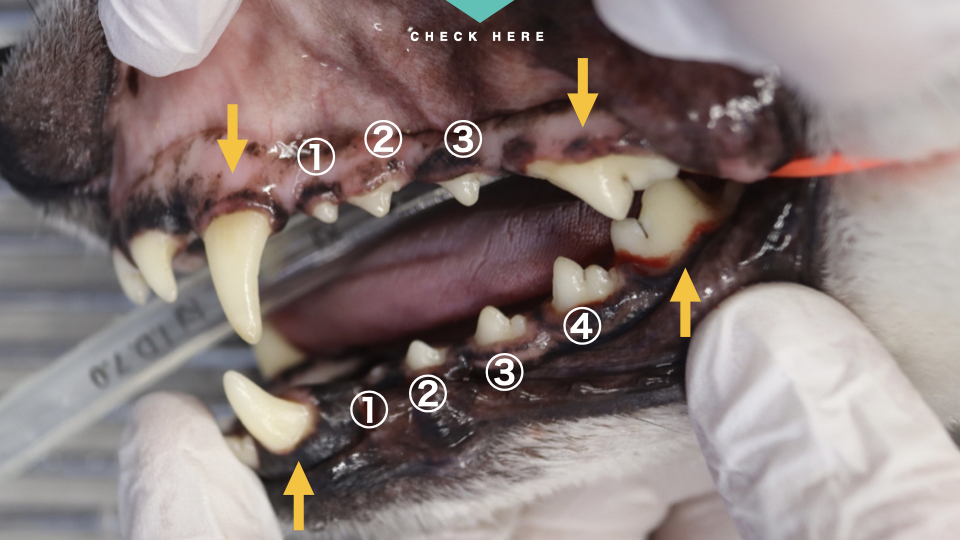

正しい歯列は下の写真をご参照ください。